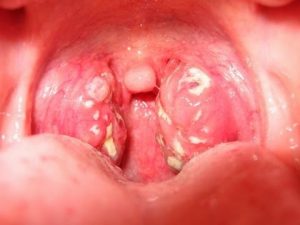

• Khi khám thường thấy amidan sưng to và đỏ, mọc mủ bao xung quanh bề mặt amidan, sưng hạch bạch huyết.

hình ảnh amidan bị sưng lên